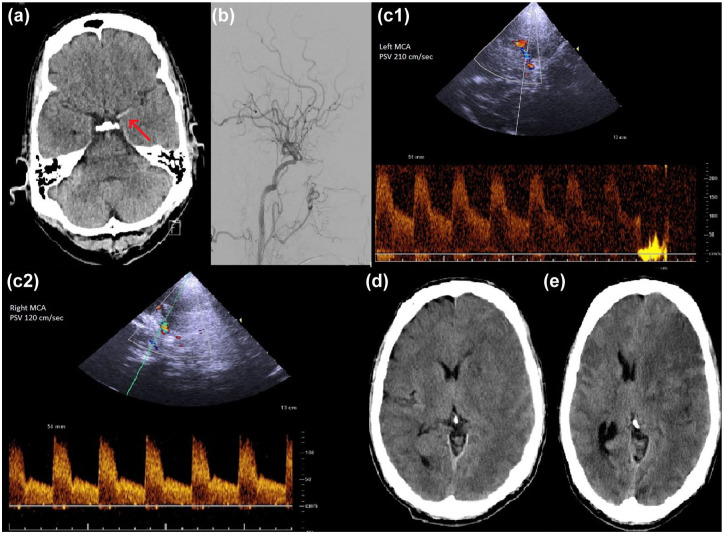

背景:急性缺血性前循环卒中大血管闭塞患者行血管内取栓术(EVT)后,经颅多普勒或双相超声(TCD)显示大脑中动脉(MCA)的峰值收缩速度(PSV)升高与功能预后不良和症状性颅内出血(ICH)风险增加有关。目的:我们评估MCA-PSV升高是否与EVT后恶性中膜梗死的发生有关。方法:我们回顾性分析了2021年1月至2024年7月在卒中中心接受急性前循环缺血性卒中EVT治疗的所有患者。TCD的MCA-PSV升高被定义为治疗侧MCA与对侧MCA相比平均PSV增加30%。恶性中膜梗死的发展根据预先确定的临床和神经影像学标准进行评估。多变量回归模型用于确定MCA-PSV与恶性中膜梗死发展之间的关系。结果:在377例患者中,49例(13.0%)发生恶性中膜梗死。在多变量分析中,MCA-PSV升高与恶性中膜梗死显著相关(优势比(OR), 53.3(95%可信区间(CI): 18.74, 151.54);结论:MCA-PSV升高可作为恶性中膜梗死发展的预测指标。TCD可以作为早期介入后监测中个体风险评估的有价值的床边工具。

Background: Increased peak systolic velocity (PSV) in transcranial Doppler or Duplex sonography (TCD) of the middle cerebral artery (MCA) after endovascular thrombectomy (EVT) for large vessel occlusion in acute ischemic anterior circulation stroke has been associated with poor functional outcome and increased risk of symptomatic intracranial hemorrhage (ICH).Objective: We evaluated whether increased MCA-PSV is associated with the development of malignant media infarction after EVT.

Methods: We retrospectively identified all patients who underwent EVT for acute anterior circulation ischemic stroke at our stroke center from January 2021 to July 2024. Increased MCA-PSV on TCD was defined as >30% mean PSV in the treated MCA compared with the contralateral MCA. The development of malignant media infarction was evaluated according to predefined clinical and neuroimaging criteria. Multivariable regression models were used to identify associations between MCA-PSV and the development of malignant media infarction.

Results: Out of a total cohort of 377 patients, 49 (13.0%) developed malignant media infarction. In multivariable analysis, MCA-PSV increase was significantly associated with malignant media infarction (odds ratio (OR), 53.3 (95% confidence interval (CI): 18.74, 151.54); p < 0.001). Furthermore, the development of malignant media infarction was also associated with secondary ICH (OR, 6.4 (95% CI: 2.16, 19.03); p < 0.001) and higher baseline National Institutes of Health Stroke Scale (OR, 1.25 (95% CI: 1.14, 138); p < 0.001).

Conclusion: Increased MCA-PSV can act as a predictive marker for the development of malignant media infarction. TCD may serve as a valuable bedside tool in individual risk assessment in early postinterventional surveillance.